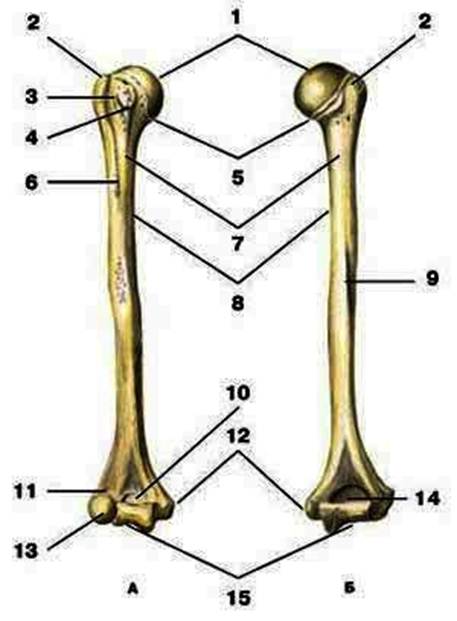

S: Цифра 1 обозначает головка плечевой кости.

S: Число 15 обозначает блок плечевой кости.

S: Цифра 5 указывает на хирургическая шейка плечевой кости.

S: Число 10 обозначает венечная ямка плечевой кости.

S: Число 14 указывает на локтевая ямка плечевой кости.

S: Цифра 9 указывает на борозда лучевого нерва плечевой кости.

S: Число 12 обозначает медиальный надмыщелок плечевой кости.

S: Стрелка указывает на большой бугорок плечевой кости.

S: Стрелка указывает на малый бугорок плечевой кости.